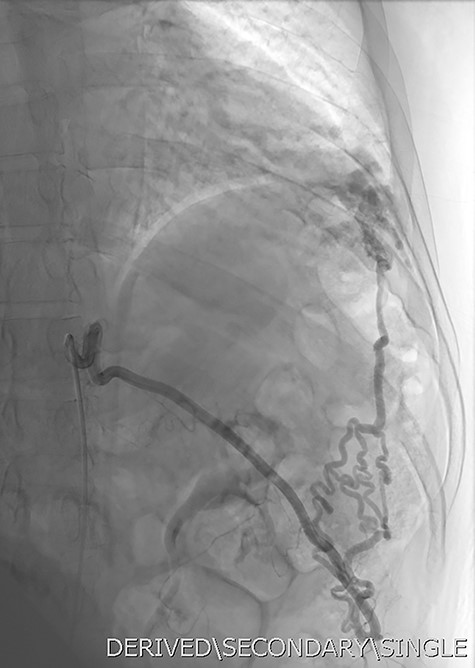

Given the findings, he was referred to Interventional Radiology for a formal digital subtraction angiogram with view of transcatheter embolization. Under local anaesthetic and sedation, a 5-french sheath was placed in the left common femoral artery. Using a 5-french pigtail catheter, aortic angiography was undertaken, confirming the CTPA findings and demonstrating predominant supply of the vascular malformation via the left intercostal arteries and the left inferior phrenic artery (Fig. 4)—draining into the left inferior pulmonary artery and vein. Superselective catheterization of the left intercostal arteries (Fig. 5) and the left inferior phrenic artery (Fig. 6) are shown. Unfortunately, due to the malformation’s volume and complexity, embolization was abandoned. He was subsequently referred to Cardiothoracic Surgery, currently awaiting consideration and workup for ligation and resection via video-assisted thoracoscopy, and potentially thoracotomy.

DSA utilizing superselective catheterization to demonstrate contribution to the PAVM via the left inferior phrenic artery, and its extensive subdiaphragmatic collateralization.